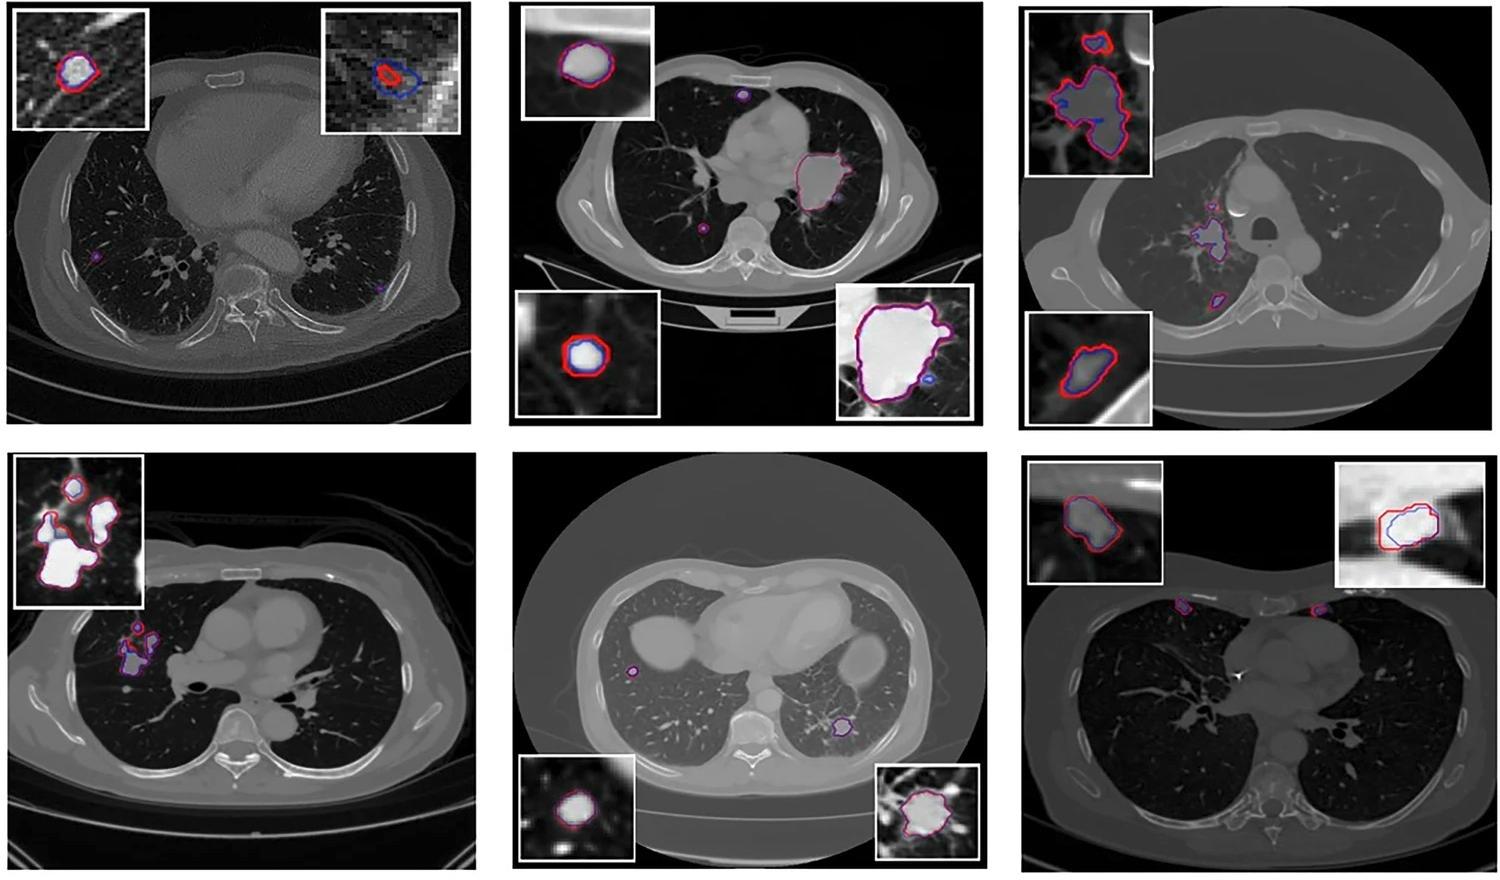

En Espagne, une équipe constituée de chercheurs de l’hôpital universitaire La Fe à Valence et de data scientists de la société d’intelligence artificielle Qibim ont réalisé une étude [1] sur la segmentation des lésions multiples du cancer du poumon. « Une segmentation précise des lésions du cancer du poumon au scanner est essentielle pour un diagnostic précis, une planification thérapeutique personnalisée et une évaluation de la réponse au traitement », rappellent-ils dans leur étude publiée au mois d’août dans la revue European Radiology Experimental. Depuis plusieurs années, des outils automatisés de segmentation des lésions pulmonaires intégrés au flux de travail radiologique ont été développés et étudiés, « mais la capacité à segmenter plusieurs lésions par patient reste sous-explorée », constatent-ils.

Dans cette optique de recherche, les scientifiques espagnols ont voulu mettre au point une méthode automatisée basée sur l’apprentissage profond pour la segme